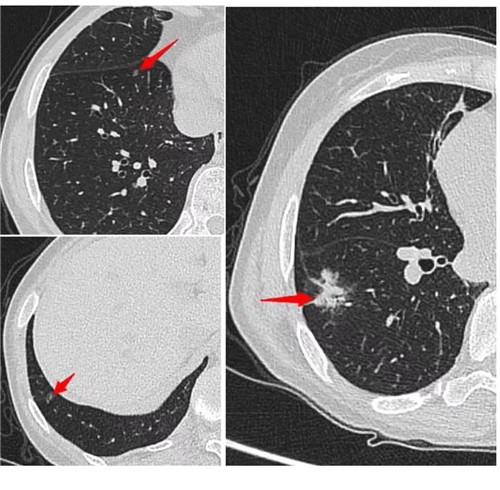

經(jīng)過術(shù)前充分評估,崔凱主任決定一次手術(shù)同期為患者切除雙肺總共六枚結(jié)節(jié)。手術(shù)團隊?wèi)?yīng)用minics肺結(jié)節(jié)三維重建分析及術(shù)前CT引導(dǎo)下錨針穿刺定位等先進工具,精準(zhǔn)定位患者雙肺的6枚磨玻璃結(jié)節(jié),其中最大的2cm,最小的0.6cm。

術(shù)前各項準(zhǔn)備完畢,崔凱主任為患者行“單孔胸腔鏡右肺下葉切除術(shù) 淋巴結(jié)清掃術(shù) 單孔胸腔鏡左肺上葉尖后段切除術(shù) 左肺下葉背段切除術(shù) 淋巴結(jié)清掃術(shù)”,一次手術(shù)成功將患者兩側(cè)肺部6枚結(jié)節(jié)全部切除,術(shù)后病理結(jié)果提示六枚結(jié)節(jié)均為早期肺癌。